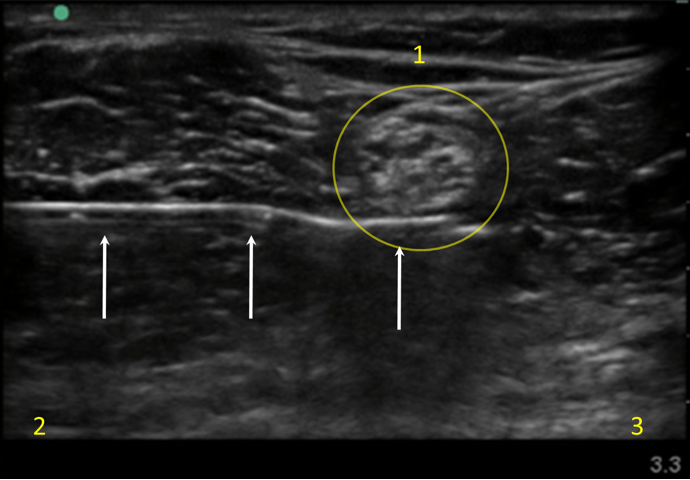

Popliteal Sciatic Nerve Block Injection Image

Tibial Nerve

Lateral

Medial

Arrows: Needle